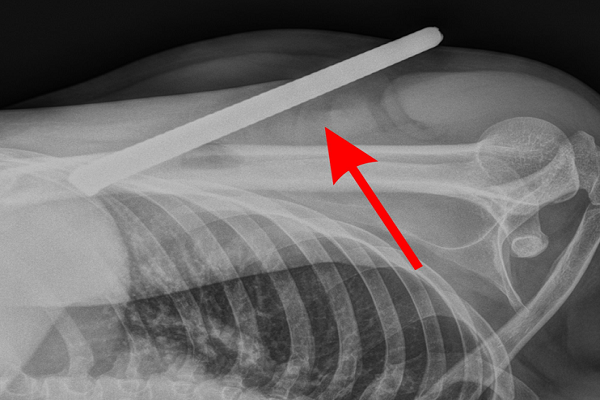

Kết quả chụp X-quang cho thấy, thanh sắt xuyên từ 1/3 trên xương cánh tay phải xuống gần đầu dưới, gây đứt một phần gân cơ nhị đầu và gân cơ tam đầu – hai cấu trúc đóng vai trò thiết yếu trong vận động chi trên

Kết quả thăm khám ban đầu cho thấy thanh sắt xuyên từ phía sau cánh tay, phần đầu không lộ ra ngoài, chứng tỏ dị vật đã cắm sâu vào các cấu trúc cơ.

Tại phòng mổ, ê-kíp ghi nhận mức độ tổn thương nghiêm trọng hơn so với dự kiến ban đầu. Thanh sắt xuyên từ 1/3 trên xương cánh tay xuống gần đầu dưới, gây đứt một phần gân cơ nhị đầu và gân cơ tam đầu – hai cấu trúc đóng vai trò thiết yếu trong vận động chi trên.